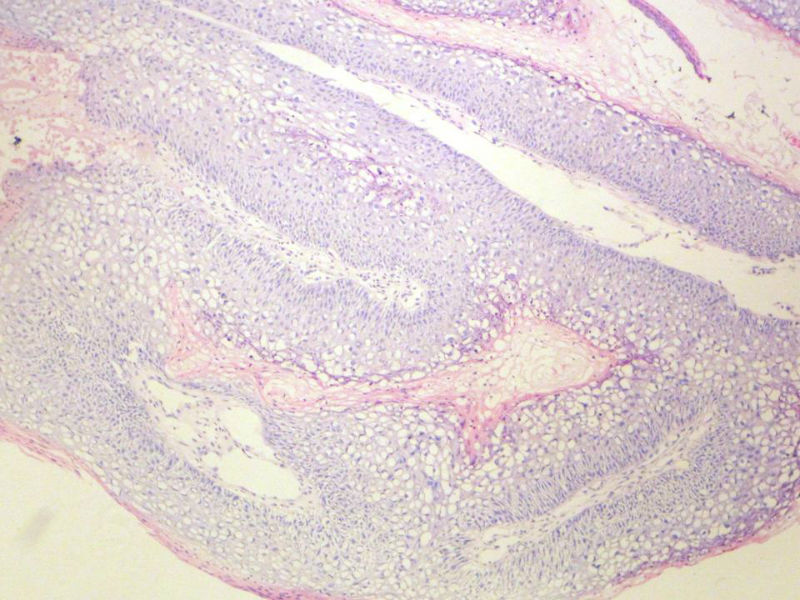

男,72岁,右耳听力下降两个月,检查右外耳道有黄豆大肿物,表面乳头状,手术切除。

请教:此例的组织像有恶变可能性吗?

乳头状瘤,有轻度异形,有恶变倾向

乳头状瘤,轻度异形,有恶变倾向

鳞状上皮乳头状瘤,未发现恶性变。